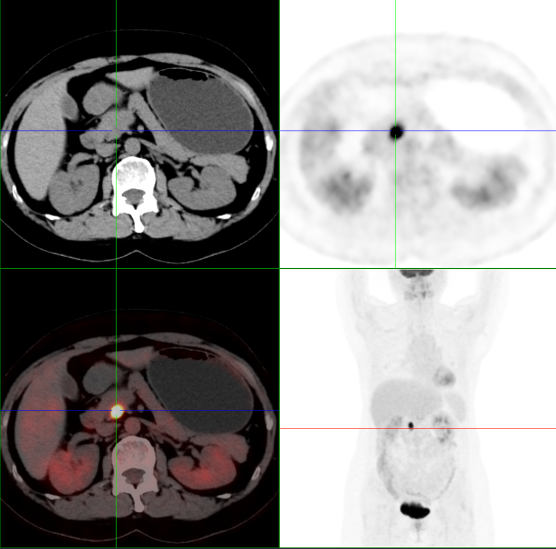

胰腺钩突病灶糖代谢明显增高,周围边界清晰,胰管或胆管未见扩张

孰料,检查结果让人大惊失色,PET/CT检查显示:胰腺钩突恶性肿瘤,肿瘤1.6cm,考虑神经内分泌肿瘤可能性大。检查结果出来之后,该科马上通知陈女士,并与其家属讲解,这一“噩耗”犹如晴天霹雳,陈女士立刻取消了旅行计划,按医生的建议进行手术治疗,不幸中的万幸,该肿瘤为胰腺神经内分泌肿瘤NET G2(早期),且未侵犯胰管或胆管,由于发现的早,所以手术治疗相对简单,而且预后也会比较好。